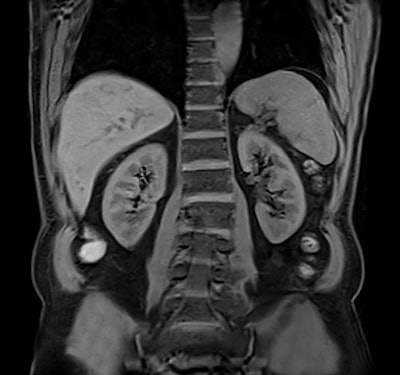

Abdominal MR scan taken on the 1.5-tesla Altea system using Caipirinha, a parallel imaging acquisition technique. Image courtesy of Siemens Healthineers."With rising patient volumes in the face of falling reimbursement, there is a clear need for greater efficiency and productivity. At the same time, the quality of exam results should not diminish," said Jan Chudzik, head of global product marketing for MRI at Siemens Healthineers, noting that there was a 20% reimbursement cut in Switzerland for imaging from 1 January 2018 and a 30% drop in reimbursement for neuro MRI over the past five years in the U.S., for example.